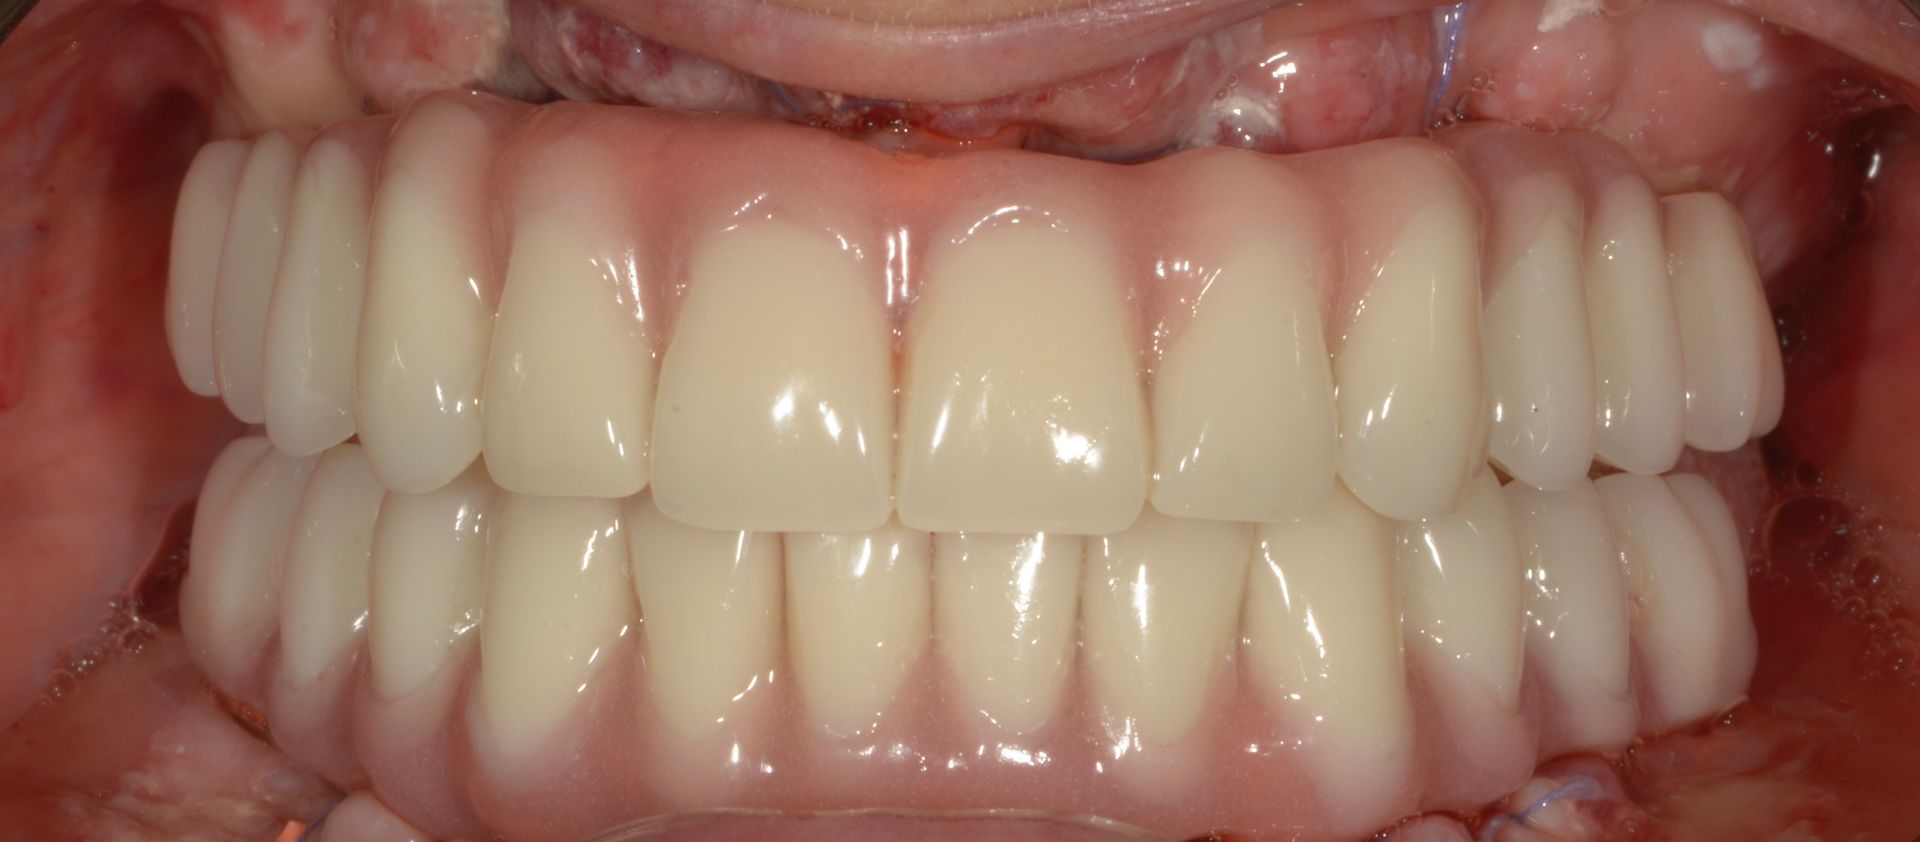

Il paziente era molto amareggiato perché non tollerava la protesi totale e aveva dolori dovuti agli impianti infetti dell'arcata inferiore. Dopo un attento studio del caso, in cui sono state studiate le forme e le altezze delle nuove protesi e abbiamo eseguito una pianificazione digitale dell'intervento chirurgico impiantare abbiamo inserito 5 impianti nel superiore con una rigenerativa orizzontale e 4 impianti nell'inferiore. a distanza di 4 ore dall'intervento abbiamo caricato gli impianti con le protesi provvisorie a carico immediato fatte con resina e una struttura in titanio, a distanza di 6 mesi sono state sostituite con 2 arcate titanio zirconio.